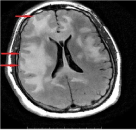

MRI of the brain was performed with and without contrast and showed multiple hyper-intense lesions involving the basal ganglion, thalamus, midbrain, pons, temporal lobe, occipital lobe, and enhancing corpus callosal lesions. There was no evidence of edema, necrosis, or ring enhancement, as shown in Figure 1. Lesions were found to cross the midline via the corpus callosum.

Figure 1: MRI of the brain a) Axial FLAIR showing corpus callosal lesion; b) Axial DWI of corpus callosal lesion; c) Axial FLAIR showing midbrain and temporal lobe lesion; d) Axial DWI of midbrain and temporal lobe lesion; e) Axial FLAIR showing thalamus and basal ganglion lesion; f) Axial T1 contrast showing enhancement of corpus callosal lesion; g) Coronal T1 contrast showing enhancement of corpus callosal lesion. View Figure 1